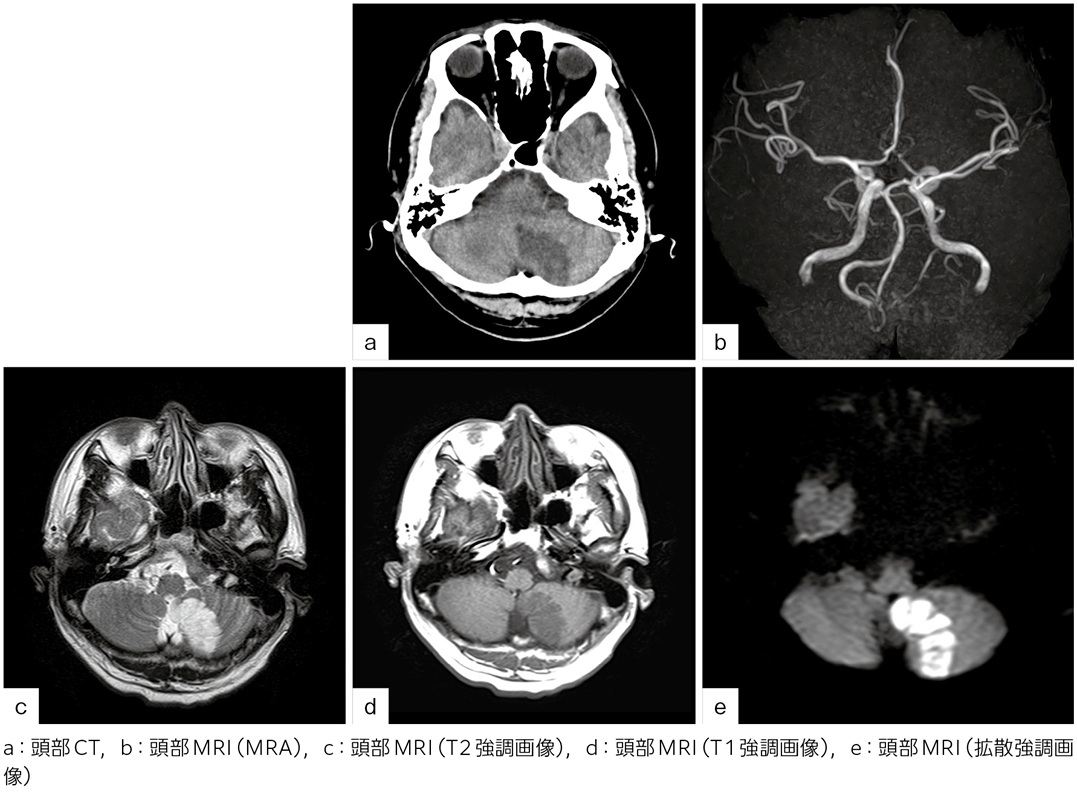

2日前に突然のめまいと強い頭痛を自覚したが,そのまま放置して仕事をしていた。その後,めまいは軽快したものの頭痛は持続し,不安を感じて近くの病院を受診。頭部CT(図a),MRI(図b~e)にて,小脳の異常が指摘され,当院へ紹介された。